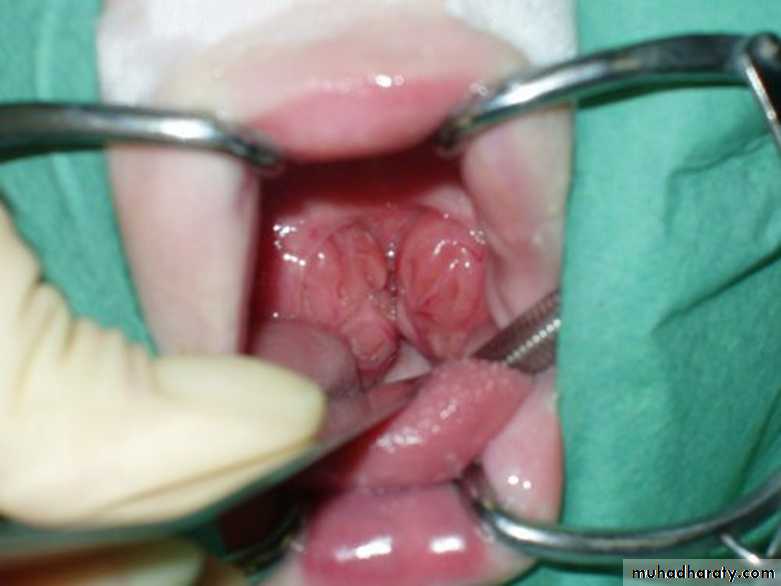

A- myringotomy with or without tympanostomy tube insertion(grommet)

B- adenoidectomy.

C- myringotomy with adenoidectomy

Adeno – Tonsellectomy&Myringotomy tube insertion (T&A &TUBES)Otosclerosis